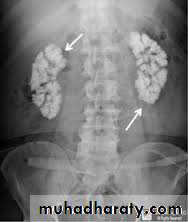

Cystic renal disease

medullary sponge kidney (MSK)MSK is a cystic condition of the kidneys characterized by dilatation of the distal collecting ducts associated with the formation of multiple cysts and diverticula within the medulla of the kidney.

The renal medulla resembles a sponge in cross-section because of dilated collecting ducts in the renal papillae and the development of numerous small cysts. This is associated with urinary stasis and the formation of small calculi within the cysts.

It has a reported familial inheritance and is associated with other malformations (hemihypertrophy).